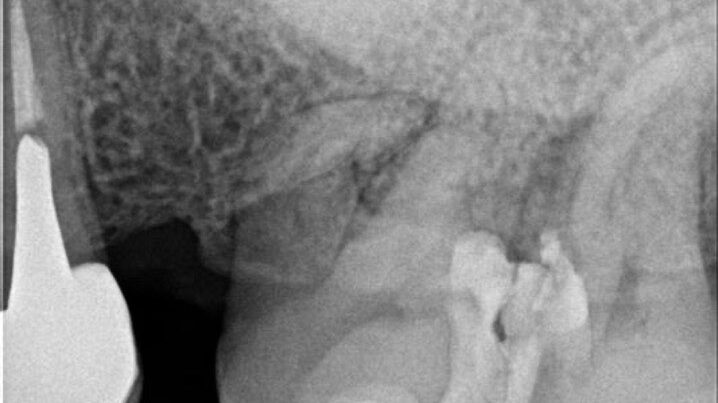

Los casos de retratamiento a menudo se complican y es por eso por lo que el retratamiento requiere…